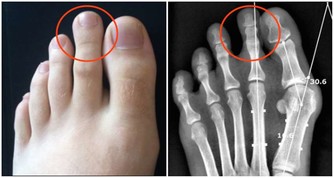

症狀嚴重但還不至於手術切除時,也可以考慮膠圈套紮法,即在痔瘡根部套入小型膠圈,痔瘡逐漸缺血、壞死。

紅外線光凝、冷凍等,都是通過冷熱刺激,直接使痔瘡壞死。

當症狀嚴重影響患者生活的時候,就要在專業醫生的指導建議下,進行必要的痔瘡切除手術了。